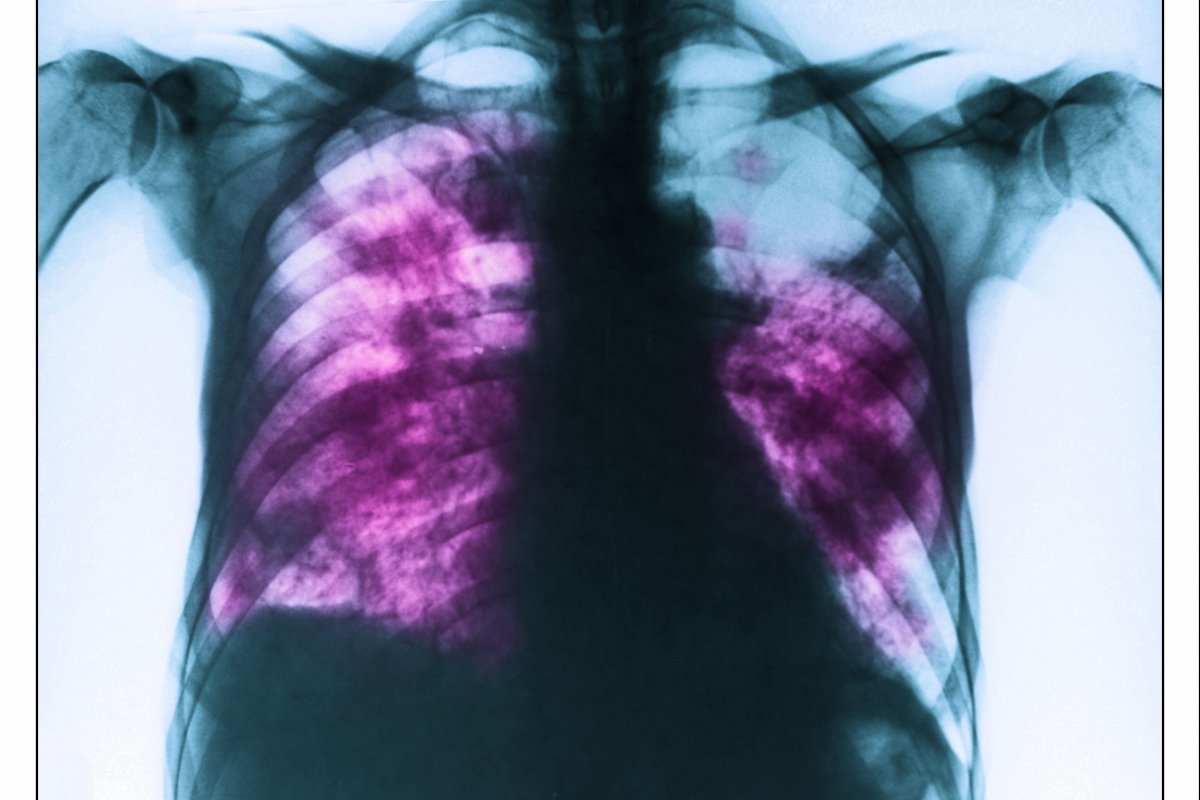

사진=게티이미지코리아.

환자는 기존에 복용 중이던 약물이 없었으며, 피부보다는 눈, 입, 생식기 등 점막 중심의 증상이 두드러졌던 점이 주요 단서였다. 의료진은 혈액 검사 및 흉부 X선 검사를 통해 MIRM으로 최종 진단을 내렸다.